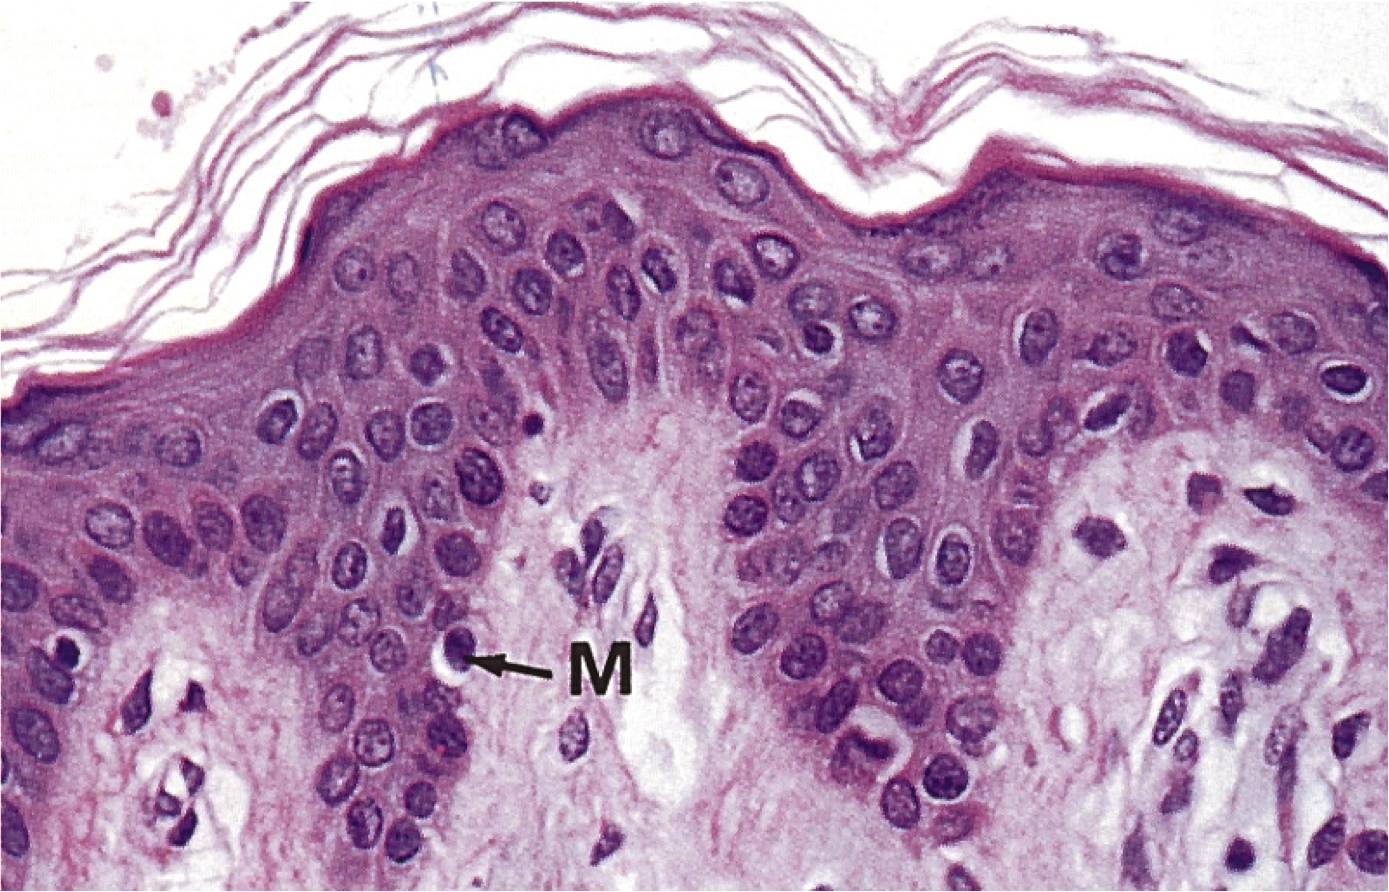

Гистология эпидермиса: структура и функции клеток кожи